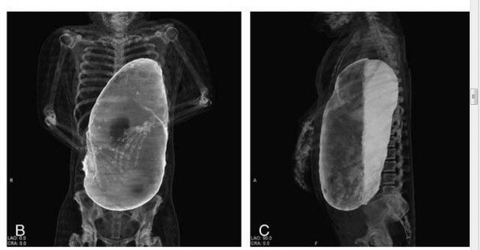

[스크랩] [기타]20인분 넘게 먹고 사망한 사람의 X 레이 사진

위가 40~50배로 커져 심장으로 들어가는 혈관을 눌러 혈류장애로 사망